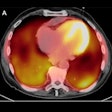

Keto diet improves PET/CT of cardiac sarcoidosis